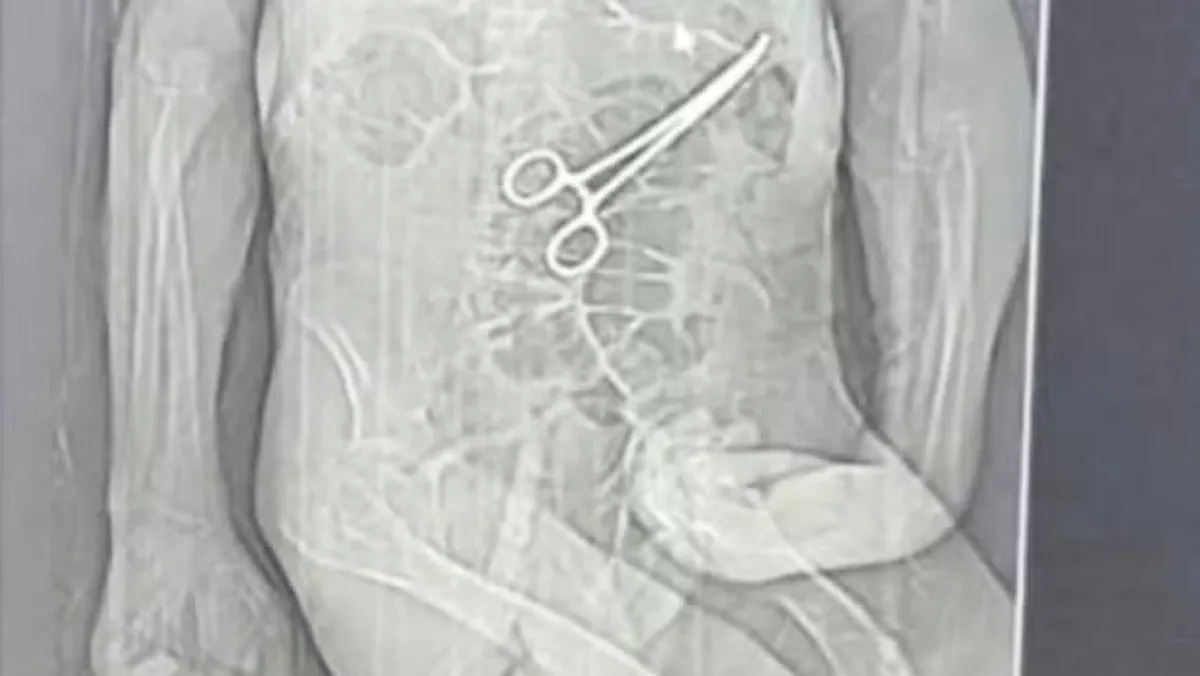

Investigação em MG: Idoso Morre Após Cirurgia com Instrumento Esquecido

A Secretaria de Saúde de João Pinheiro, localizada no Noroeste de Minas Gerais, instaurou uma sindicância para investigar a morte de um idoso que teve um instrumento cirúrgico deixado dentro de seu corpo durante uma cirurgia realizada em uma unidade de saúde local. O caso, que gerou grande comoção na comunidade, levanta sérias preocupações sobre a segurança nos procedimentos cirúrgicos.

O advogado da família de Manoel informou que ações legais foram iniciadas após a divulgação de um exame de tomografia, que revelou a presença do instrumento cirúrgico no corpo do paciente. Essa descoberta levantou sérias questões sobre a responsabilidade do hospital e os protocolos seguidos durante a cirurgia.

A família alega que a pinça cirúrgica foi esquecida dentro do corpo de Manoel após a primeira cirurgia, uma situação que, segundo eles, só foi confirmada após a morte do idoso. A Secretaria Municipal de Saúde de João Pinheiro confirmou que houve a retirada de um objeto durante a cirurgia, mas argumentou que Manoel estava em estado crítico e apresentava múltiplas comorbidades.